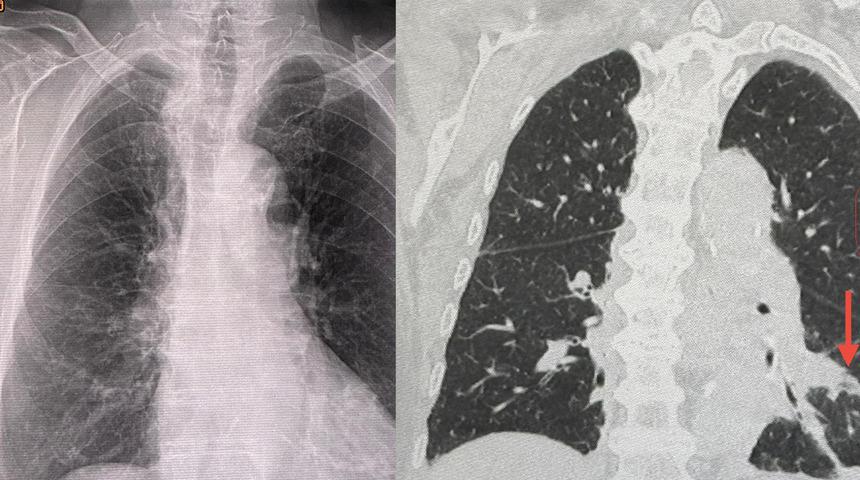

Tedaviye alınmadan ve röntgen çekilmeden önce, ateş, öksürük ve balgamla kendini hasta hissetmeye başladı. Sol akciğerde nekroz vardı. Doktorlar akciğerlerinde bakteriyel enfeksiyon olduğu sonucuna vardılar. Bu durumun klima mikroplarından kaynaklanabileceği sonucuna vardılar. Doktorlar tanı olarak ise, "zatürreye neden olan Legionella pneumophila bakterisiyle enfeksiyon" ifadelerini kullandı. 1 hafta süren tedavinin ardından 88 yaşındaki hastanın iyileştiği ifade edildi.

Aylardır kapalı olan odada kaldıktan 2 gün sonra ateşinin çıkmaya başladığını söyleyen 88 yaşındaki hasta, "İki gün sonra ateşim çıkmaya başladı. İlk başta berrak bir balgamım vardı. Daha sonra daha fazla balgamım oldu, yorgundum, burun akıntım yoktu, boğaz ağrım yoktu, baş ağrım yoktu, vücudumda ağrılar yoktu. Tedavi için Pak Chong yakınlarındaki bir hastaneye gittim. Göğüs röntgeni çektiler. Sol alt tarafta bir anormallik bulundu" dedi.